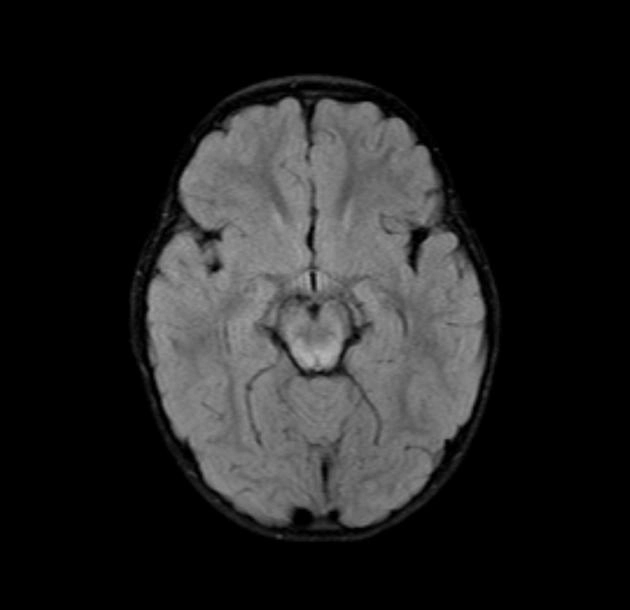

Bệnh não ty thể (Mitochondrial Encephalopathies -ME)

Rối loạn ty thể nguyên phát (Primary mitochondrial disorders - PMDs)

Các biểu hiện ở não của bệnh mucopolysaccharidoses (Cerebral manifestations of mucopolysaccharidoses)

Bệnh loạn dưỡng chất trắng tế bào hình cầu (Globoid Cell Leukodystrophy)/ Bệnh Krabbe

Bệnh Fabry (Fabry Disease)

Rối loạn Peroxisome (Peroxisomal Disorders)/Hội chứng Zellweger (Zellweger Syndrome)

Bệnh nước tiểu mùi si-rô phong (Maple syrup urine disease - MSUD)

Bệnh Canavan (Canavan Disease)

Bệnh loạn dưỡng chất trắng thượng thận liên kết nhiễm sắc thể X (X-linked Adrenoleukodystrophy)

Nhiễm toan glutaric type 1 (Glutaric aciduria type 1)

Bệnh Loạn dưỡng chất trắng thể não to kèm nang dưới vỏ (Megalencephalic Leukoencephalopathy with Subcortical Cysts - MLC)

Thoái hóa thần kinh với tích tụ sắt trong não (Neurodegeneration with Brain Iron Accumulation - NBIA)

Thoái hóa thần kinh liên quan đến Pantothenate Kinase (Pantothenate kinase-associated neurodegeneration - PKAN)

Huntington Disease - HD

Bệnh loạn dưỡng chất trắng dị sắc (Metachromatic Leukodystrophy - MLD)

Bệnh Wilson- Biểu hiện ở não bộ (Wilson Disease)